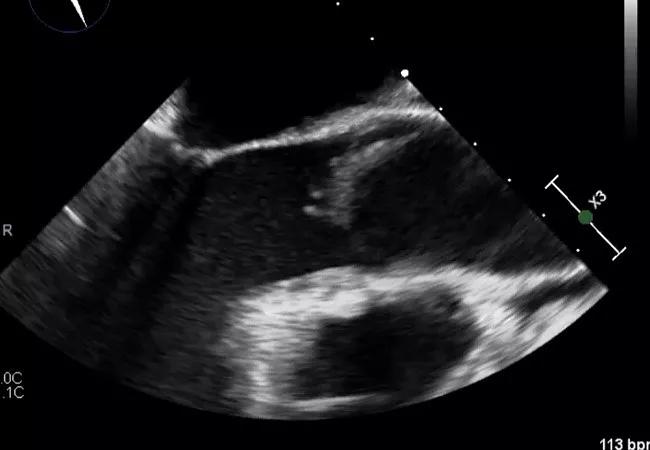

Vegetation size. The larger the vegetation, the greater the risk of embolism. This is illustrated in the two echo images below, both of which are from patients with native aortic valve endocarditis. The long-axis view on the top shows a very large vegetation that appears ready to break off at the stalk, whereas the echo on the bottom shows a smaller vegetation with lower risk of detachment.

The below echoes are illustrative, with the upper image showing a large vegetation on the medial aspect of the anterior leaflet of a native mitral valve while the lower image shows a layering infected thrombus on a bioprosthetic aortic valve.

Number of vegetations. The more vegetations, the higher the likelihood of embolization. The images below demonstrate two echocardiographic manifestations of native mitral valve IE that differ by number of vegetations, with the upper panel showing multiple vegetations on both the anterior and posterior leaflets and the lower panel showing one predominant large vegetation on the lateral aspect of the posterior leaflet.